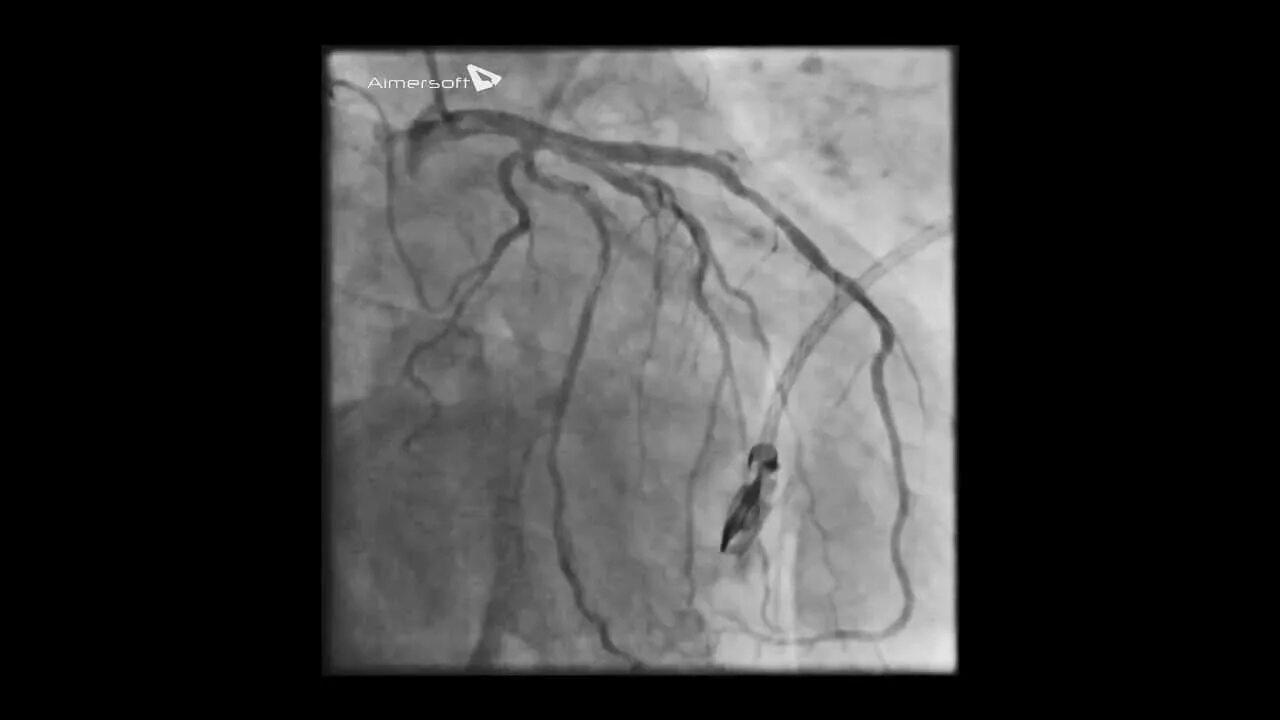

Стентирование самолет